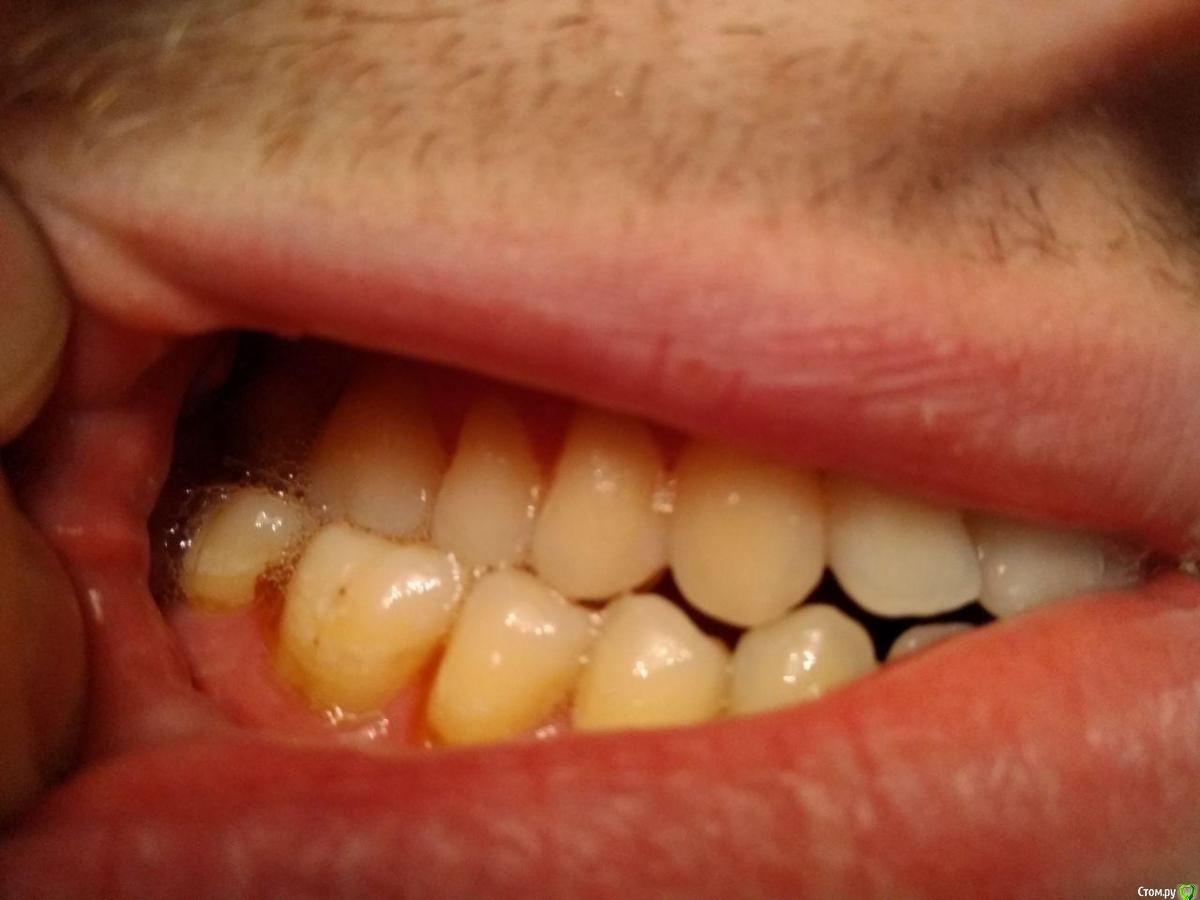

Здравствуйте, мне 29 лет, хочу остаться со своими зубами и не угробить ВНЧС.

С 16-20 лет проходил лечение у ортодонта (2 года расширитель на верхней челюсти, 2 года брекеты). Итог - получили, так называемый камуфляж (как я сейчас понимаю).

В данный момент ситуация усугубилась, основные проблемы - множественные рецессии и хруст в ухе при глотании.

2ой Провел диагностику, ТЭНС терапию, сделал капу на нижнюю челюсть (хруст при зевании прекратился, при глотании все равно слышно), про  рецессию было сказано, что некоторые зубы получают неправильную нагрузку, но причина именно множественной рецессии не в прикусе. Дальнейшие предложении - устранение перекрестного прикуса с помощью брекетов или оклюзионного протокола.